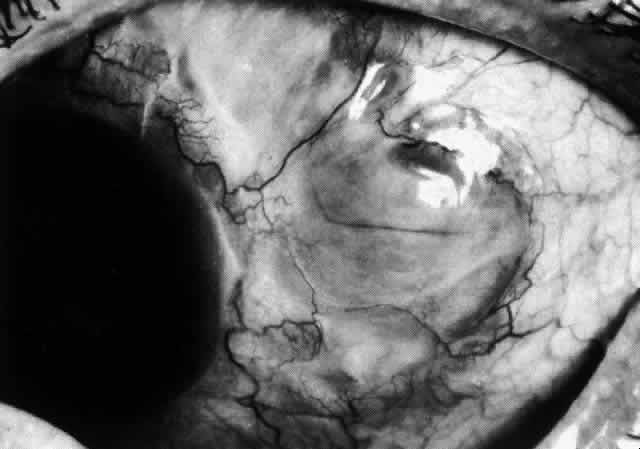

The angiogram is similar to that of diffuse anterior scleritis (i.e., there is a rapid filling pattern and deep scleral leakage of dye).26 Necrotizing Anterior Scleritis with Inflammation Patients with necrotizing anterior scleritis with inflammation not only suffer extremes of discomfort but are in serious danger of losing an eye. Therefore, it is of great importance that the condition be detected early and treated adequately. (It is of equal importance that those varieties of scleral inflammation that are not destructive to the eye should not be treated with drugs that are themselves dangerous.) Accurate diagnosis is the key. Necrotizing scleritis accompanied by inflammation is always painful, waking the patient at night, increasing in intensity day by day, and leading to severe distress. The sclera is swollen, and the overlying inflammation is localized to the center of a lesion or to either end of an extending lesion (Fig. 37; Color Plate 1D). After inflammation, the sclera becomes transparent so that the underlying choroidal pigment becomes visible when viewed in daylight (Fig. 38). These areas may be invisible with the slit lamp. The area of inflammation extends outward around the globe from the original site of inflammation, often joining with other areas of scleritis that have subsequently appeared. If the inflammation is not suppressed, the process will progress around the globe until the whole anterior segment is involved (Fig. 39).

The characteristic features of necrotizing scleritis on fluorescein angiography are hypoperfusion and, eventually, nonperfusion of the vascular networks (Figs. 40 through 43).26 The initial changes are on the venous side of the capillary network; the transit time of the dye increases even if the eye is red and congested. If the disease process persists or has been present for a long time, thrombosis and permanent vaso-occlusive changes occur. These vessels (or the occluded capillary network) are bypassed by the opening of anastomotic channels. New vessels in a granuloma give rise to deep intrascleral leakage of dye (see Fig. 43). Conjunctival and episcleral involvement by the destructive change is late but is always preceded by vaso-occlusive changes that can sometimes be detected with use of the red-free light on the slit lamp (Figs. 44 and 45).